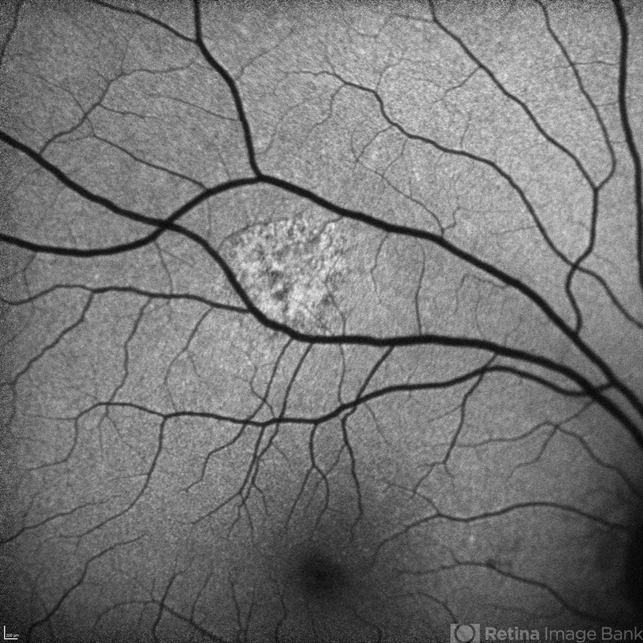

- Unilateral Acute Idiopathic Maculopathy

- Condition/keywords

- chorioretinal inflammations, unilateral acute idiopathic maculopathy, Coxsackie

- Kidron Robertson, Georgia Eye Institute of the Southeast, Savannah, GA

Optical coherence tomography system

Heidelberg Spectralis - Description

- FAF of UAIM lesion